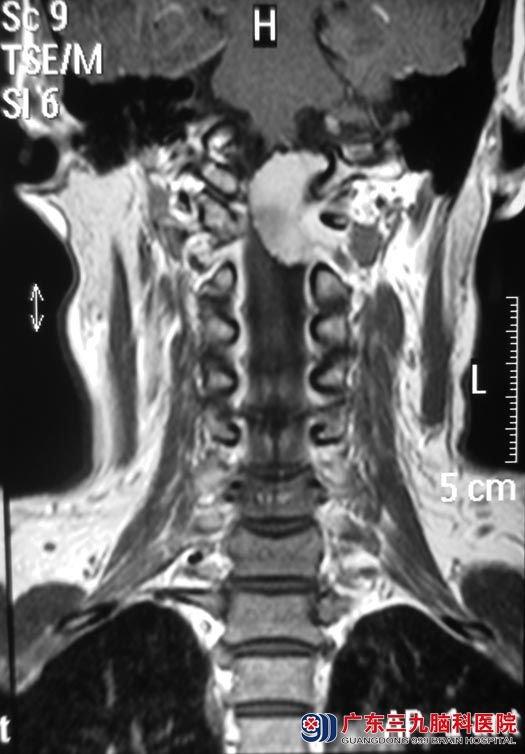

入住广东三九脑科医院综合神经外科时查体:右侧浅感觉较左侧差,悬雍垂向右侧,左侧咽反射减弱,左侧耸肩转头运动减弱,舌左偏;复查脑部MR见:枕骨大孔区级上颈段椎管内示一不规则形占位性病变,病变以宽基底与斜坡后方硬脑膜及颈1-2椎体后方硬脊膜相连,大小约20.5mm×12.0mm×32.5mm,延髓及上颈段脊髓受压、变形,并向右偏移;头颈CTA检查提示:枕大孔区占位性病变,血供较丰富,左侧椎动脉被包绕可疑。